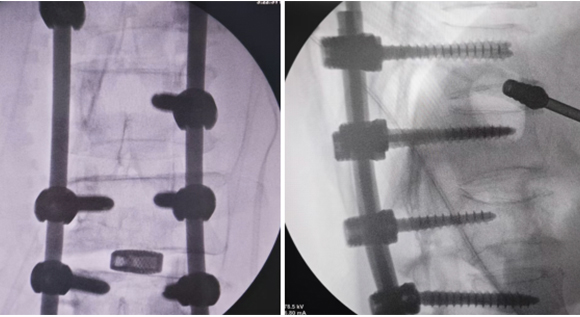

脊柱脊髓神經(jīng)微創(chuàng)中心以微創(chuàng)技術(shù)為引領(lǐng),以功能恢復(fù)為目標(biāo),主要治療脊柱外傷、腫瘤、退行性病變、脊柱畸形等疾病。團(tuán)隊(duì)利用神經(jīng)外科顯微技術(shù),結(jié)合神經(jīng)內(nèi)鏡微創(chuàng)技術(shù),對(duì)脊柱間盤變性疾病、頸腰椎管狹窄、頸腰椎間孔狹窄、頸腰椎間盤突出、頸腰椎體不穩(wěn)、脊柱骨折、寰樞椎脫位、脊柱腫瘤、椎管內(nèi)腫瘤、脊髓損傷、脊髓空洞、脊髓栓系等疾病進(jìn)行高效、特色手術(shù)治療,如顱頸交界區(qū)畸形寰枕減壓內(nèi)固定術(shù)、脊柱腫瘤全脊椎切除內(nèi)固定術(shù)、微創(chuàng)椎管內(nèi)腫瘤切除術(shù)、微創(chuàng)脊柱旁腫瘤切除術(shù)、寰樞椎脫位椎間融合內(nèi)固定術(shù)、脊柱骨折微創(chuàng)經(jīng)皮椎弓根釘內(nèi)固定術(shù)、經(jīng)椎間孔椎間融合內(nèi)固定術(shù)(MIS—TLIF)等,最大程度降低脊柱脊髓手術(shù)創(chuàng)傷,具有創(chuàng)傷小、輸血少、恢復(fù)快、口碑好,出院早等優(yōu)勢(shì)。